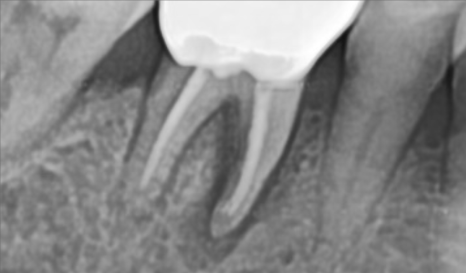

자세히 보는 작은 X-ray를 추가로 촬영합니다.

흠.. 생각보다 더 많이 심각한 상태입니다.

특히나 뿌리만 남은 치아는 내부에 골소실이 심각한 상태입니다.

한쪽은 치아 머리가 깨져서 검게 뿌리만 남아있고,

한쪽은 뿌리쪽에서 고름주머니가 잡혀있어

건들면 아프고, 매번 안좋은 냄세가 난다고 하시네요.

(촉감이 몰캉몰캉하니 고름이 차있는 상태입니다)

오래전 시행됬을 신경치료의 흔적이 보입니다..

아마 신경치료 후 크라운을 씌우셨을텐데

내부에 충치가 생겨 크라운이 머리채로 부러져나가버렸습니다.

이정도로 치아가 남지 않은 상태면 임플란트 이외에는 방법이 없습니다.